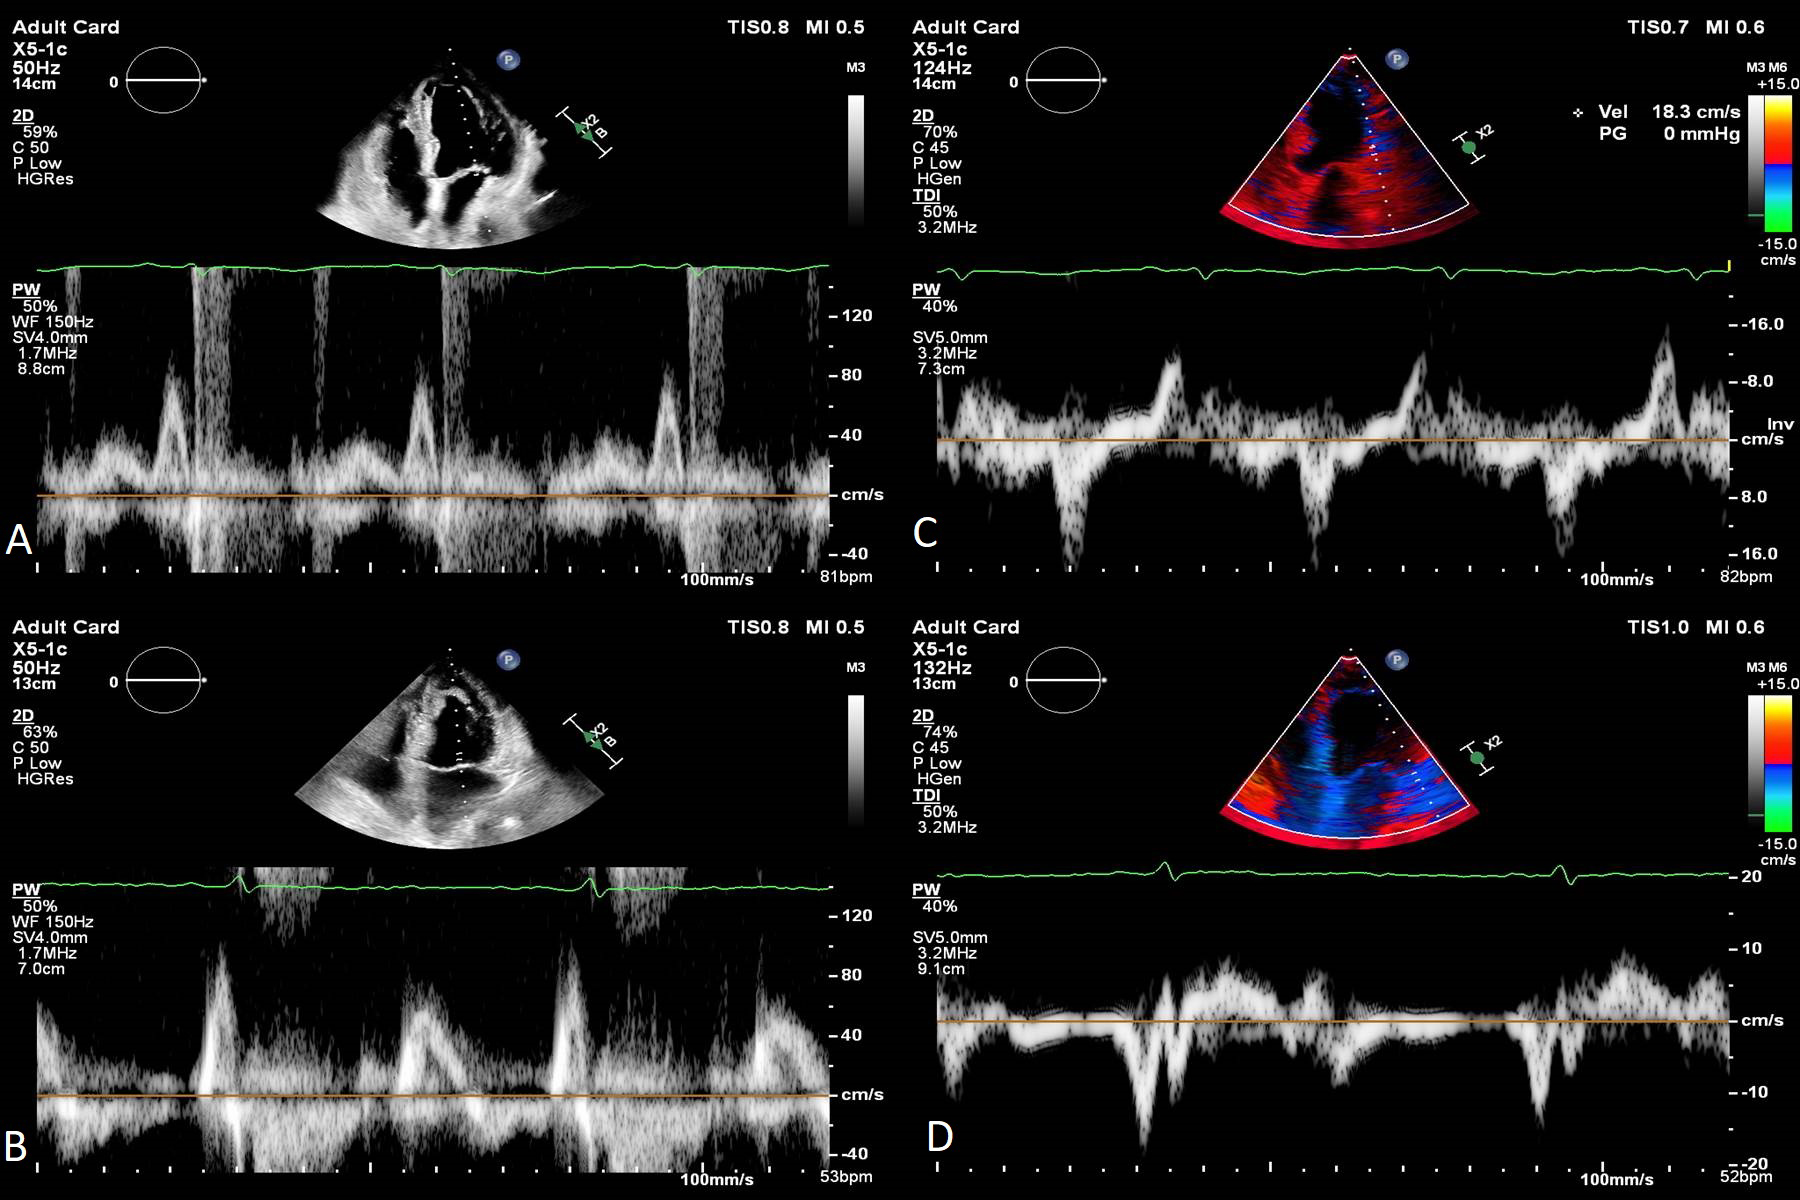

Alongside the LV systolic function, LV diastolic function needs to be evaluated in the acute phase and then at follow-up. Kumar et al. [81] revealed that LVEF improved alongside diastolic function: E value, E/A ratio and e’ values improved over time (Fig. 3). Both lower LVEF and higher E/e’ ratio were associated with in-hospital complications in TS patients [37, 54].

Fig. 3.Transthoracic echocardiography images apical four-chambers views of a 73 year-old female patient with Takotsubo Syndrome showing the evolution of diastolic function. E wave velocity progressed from 40 cm/s in the acute phase to 70 cm/s at one month follow-up, the E/A ratio from 0.5 to 0.8 (A and B). Lateral e’ velocity increased from 4 cm/s to 8 cm/s and E/e’ ratio from 10 to 8.7 (C and D). 2D, two dimensional; PW, pulsed wave doppler; TDI, tissue doppler imaging.